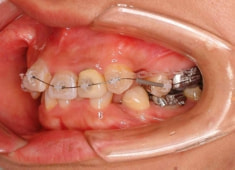

治療後(3年2ヶ月後)

治療開始から1年8ヶ月後